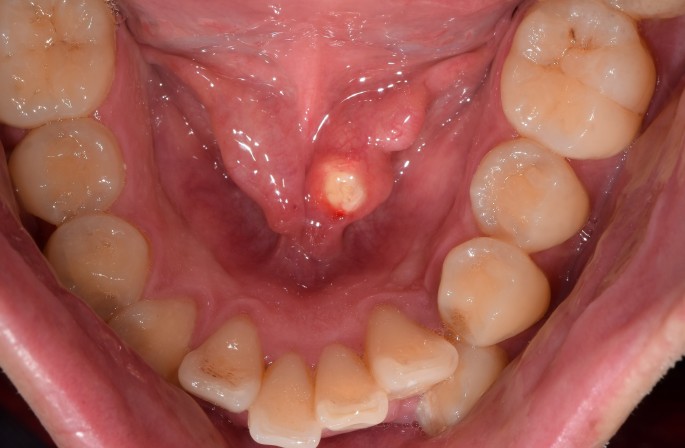

타석증은 침샘에 돌이 생기는 질환입니다. 침샘은 입안을 촉촉하게 유지하고, 음식을 소화하는 데 필요한 침을 분비하는 기관입니다. 타석증은 침샘의 어느 부위에나 돌이 생길 수 있지만, 가장 흔하게 이하선에서 가장 잘 발생합니다.

2. 증상

1) 침샘 부위 통증

2) 부기

3) 압통

4) 발적

5) 침 분비 감소

6) 음식을 씹을 때 통증